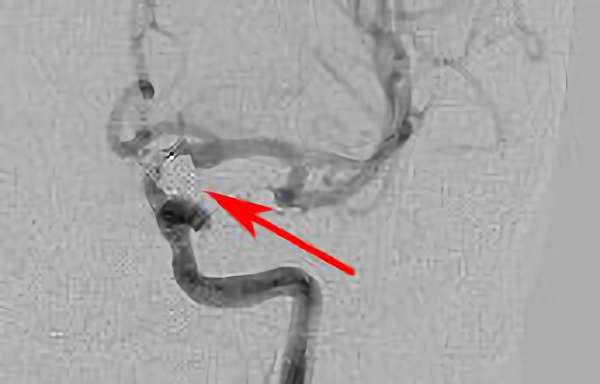

No.1627 手術後